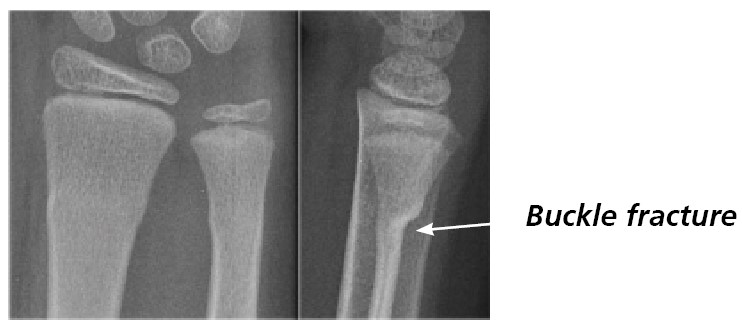

A buckle injury is a type of injury where the bone has been squashed. Children and young people’s bones are softer than adults. When they have an injury to the bone, the bone is more likely to be squashed than broken following the accident. This can result in a bump in the bone, as opposed to a clear break. (See images).

What does a buckle injury look like?